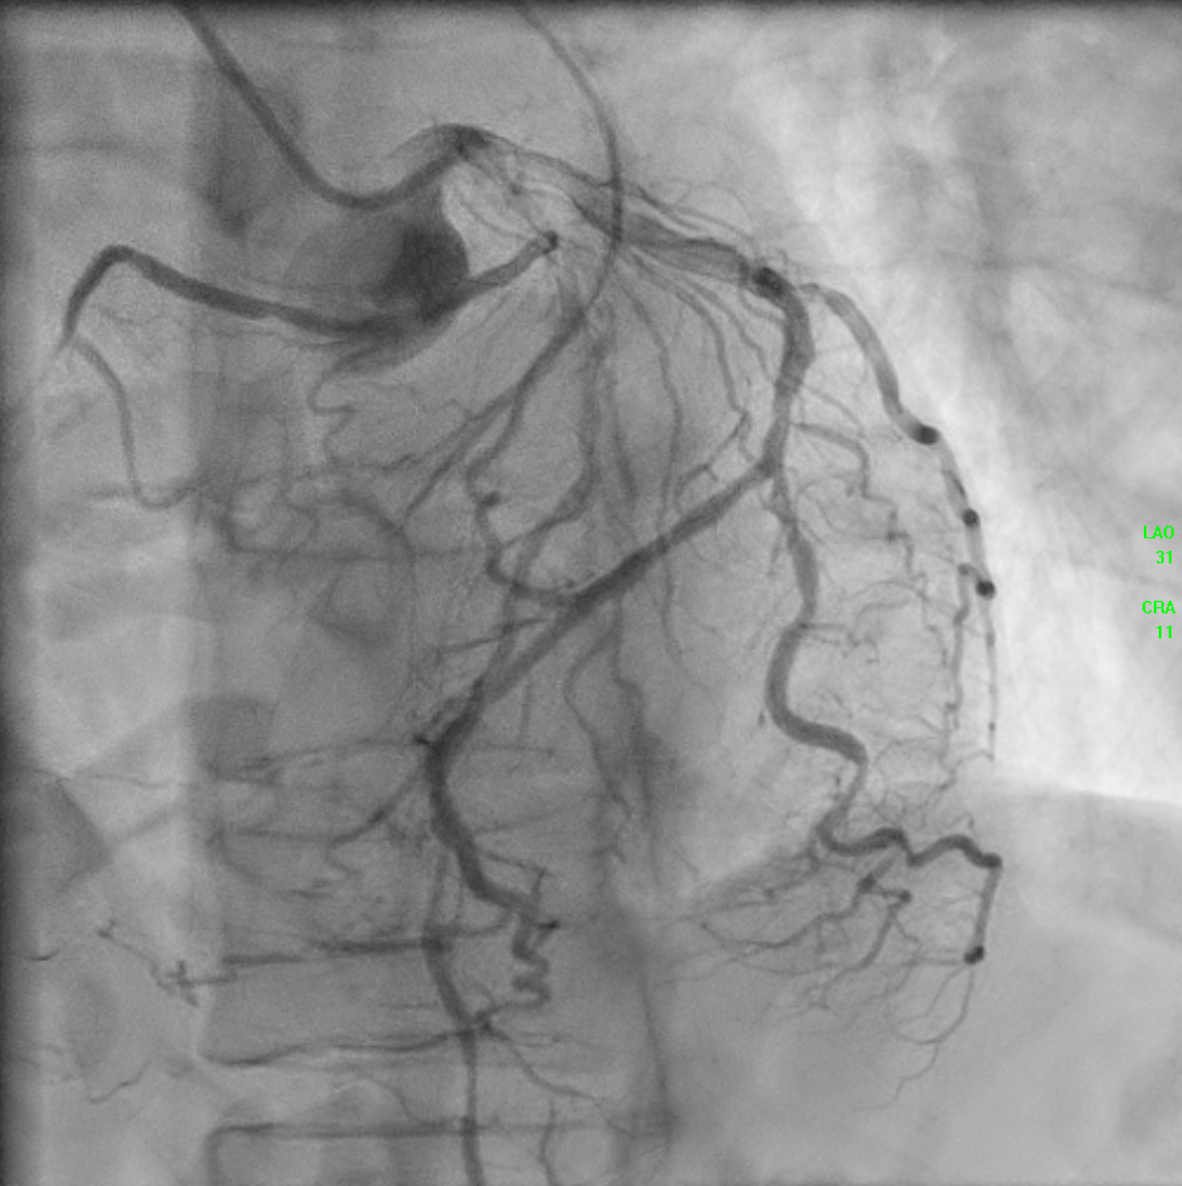

The initial angiogram on July 3rd, 2025, showed two-vessel coronary artery disease, with diffuse atherosclerosis extending from the proximal to distal LAD and moderate stenosis of the OM2. The RCA was absent and appeared to be supplied by the D1 branch, which showed severe disease at the ostium and mid segment. A repeat angiogram showed drop of blood flow with TIMI 2 flow to the distal LAD and RCAterritories. Then we proceed to PCI to LAD and RCA.

An IVUS-guided PCI of the LAD and RCA was performed via right radial access. An EBU 3.5, 7 Fr guiding catheter engaged the left main, and a Sion Blue wire was advanced to the distal LAD for pre-dilatation with a 2.5 mm NC balloon. Wiring the anomalous RCA from the LAD was challenging due to a retroflexed ostium but was achieved using a reverse wire technique with adual-lumen (Sasuke) catheter and Sion Black wire. Difficulty crossing the mid RCA, likely due to dissection, required multiple wire exchanges before reaching the distal RCA. Lesion preparation used 2.0 mm and 1.5 mm NC balloons in the RCA. IVUS showed LAD diameters of 2.5mm distally with diffuse disease and < 40%plaque burden. A hybrid revascularization strategy was planned. Further preparation involved 3.0 mm and 2.0 mm balloons in the LAD and RCA. DCBs (2.0 ¡¿25 mm in distal LAD; 2.0 ¡¿ 20 mm in RCA) were applied for 60 seconds each. A Xience Sierra 3.0 ¡¿ 38 mm DES was deployed in the proximal–mid LAD,post-dilated with 3.0–3.5 mm NC balloons and optimized with a 4.0 mm POT. IVUS revealed a distal edge dissection, covered with an additional overlapping Xience Sierra 2.75 ¡¿ 23 mm DES. Final IVUS confirmed good stent expansion (MSA6 mm©÷), and angiography showed non–flow-limiting distal LAD dissection with TIMI 3 flow in both LAD and RCA.